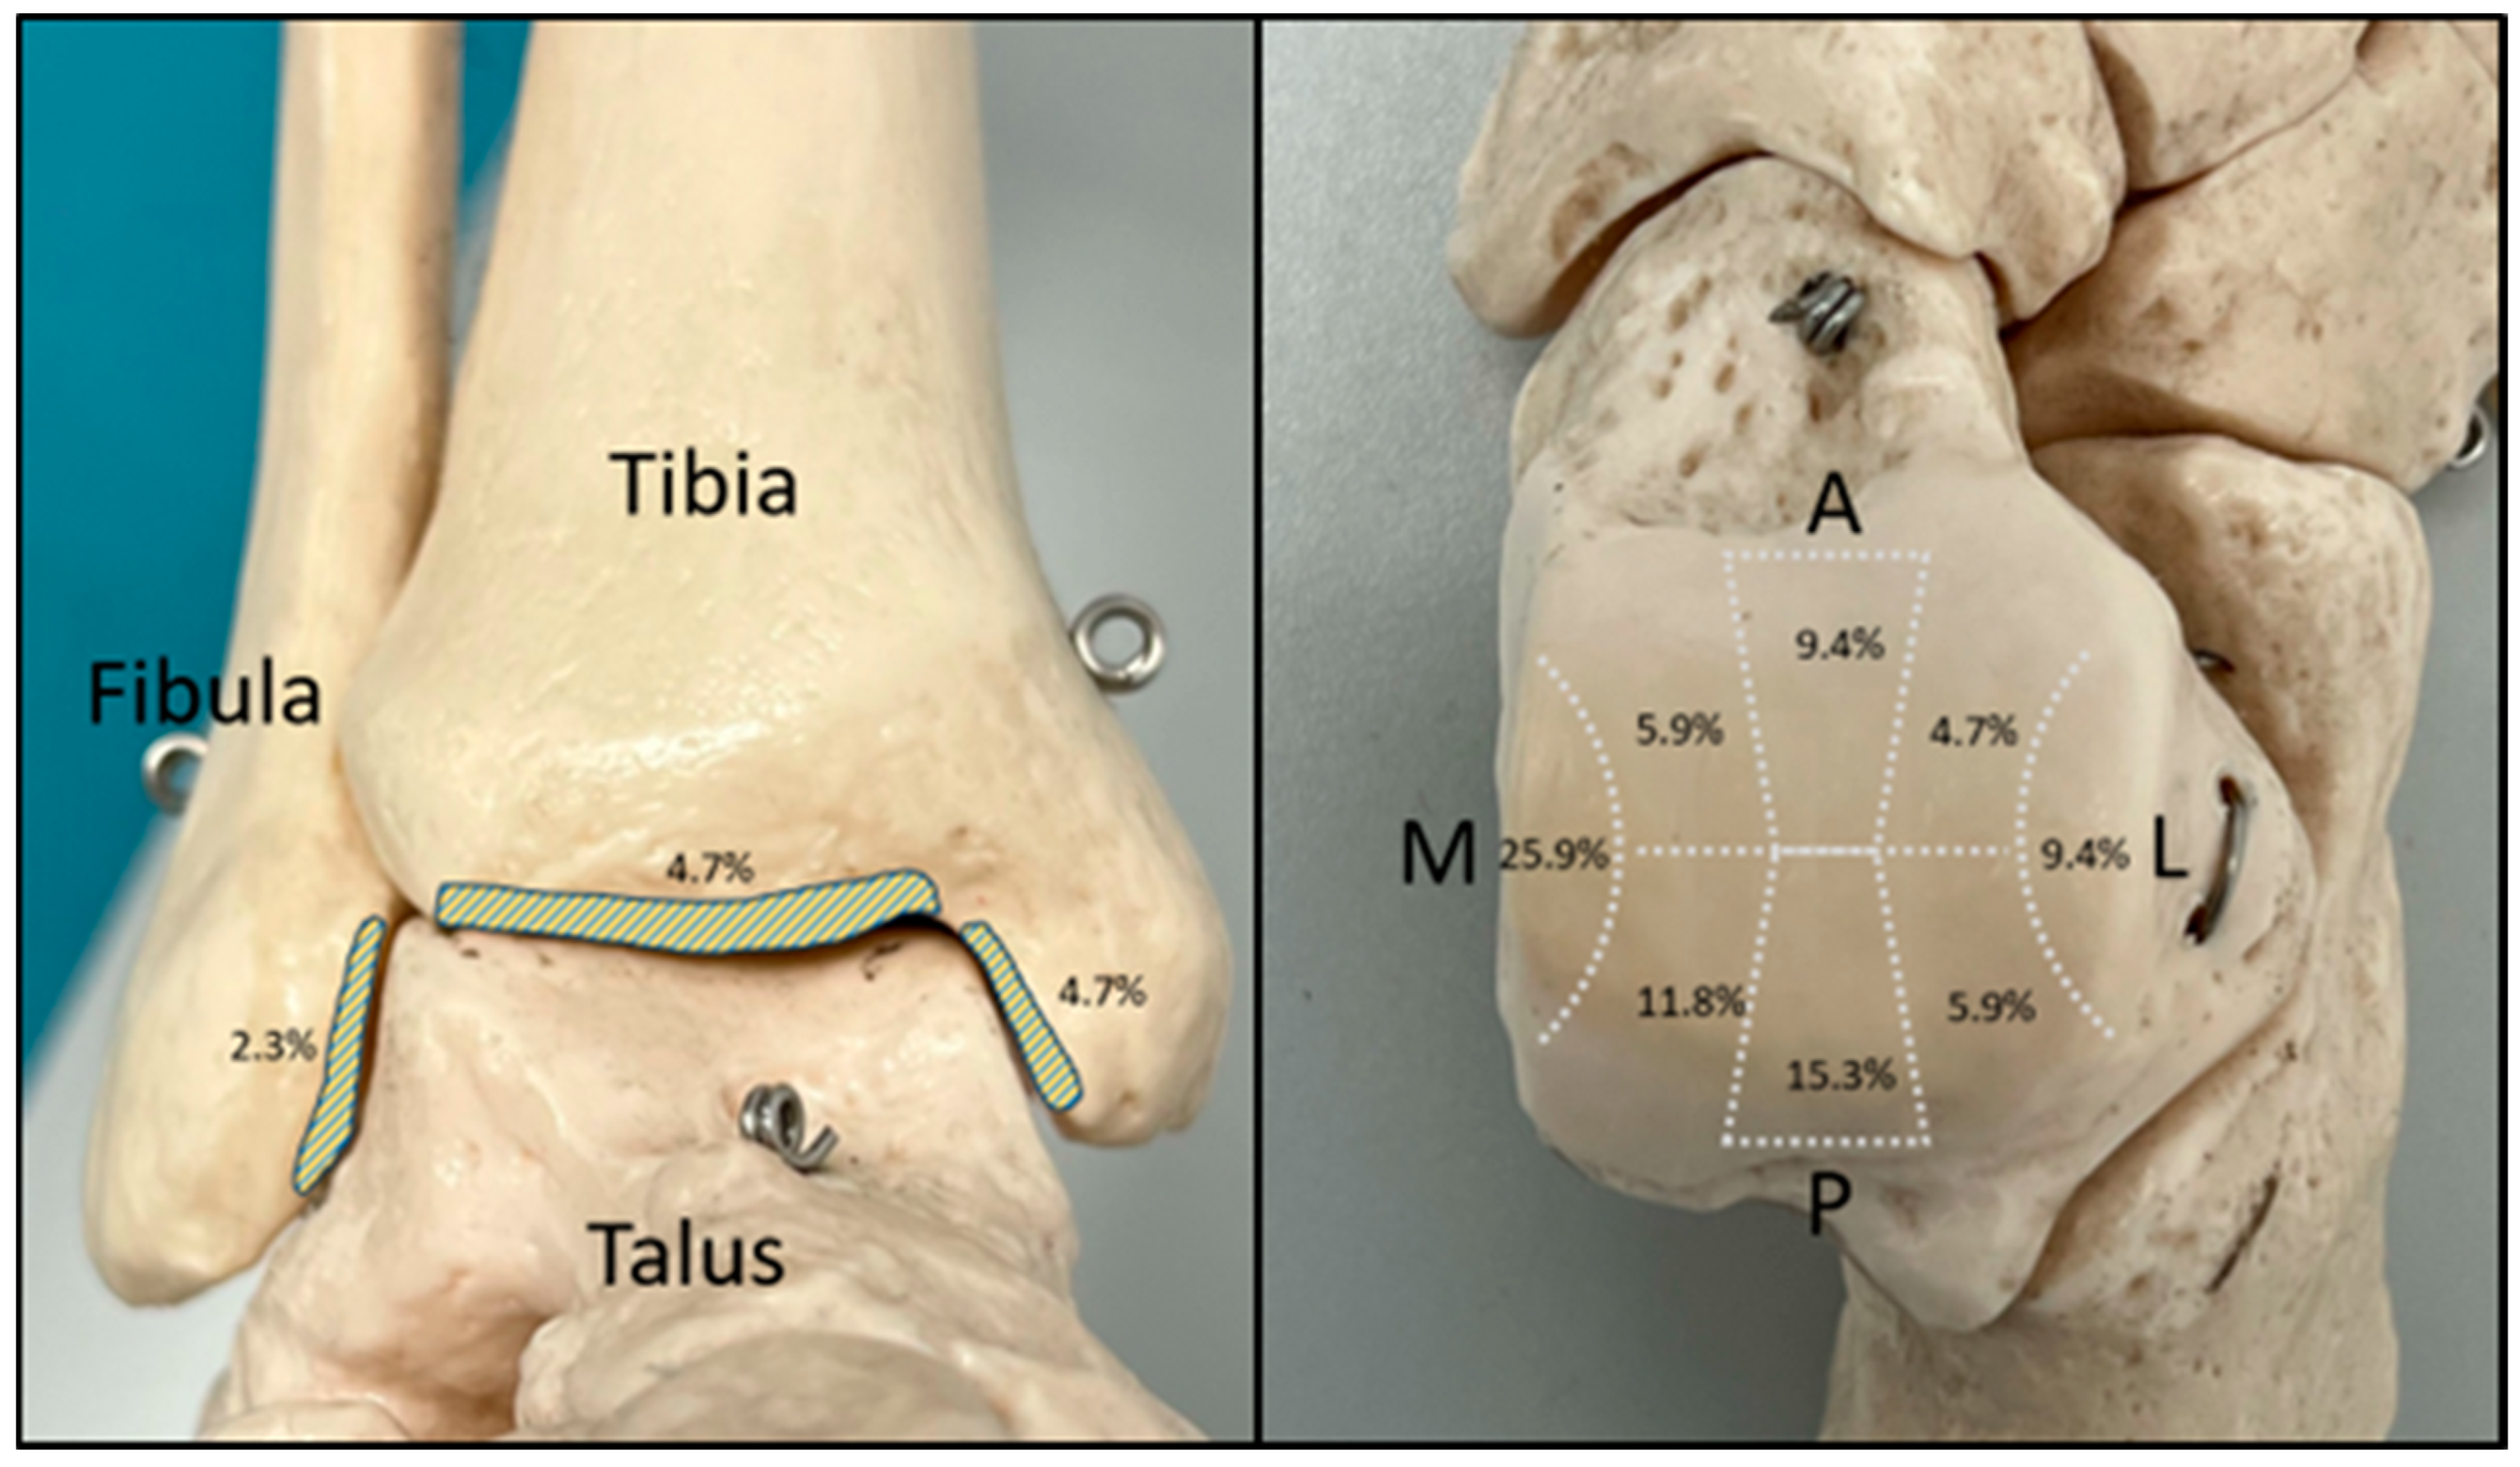

2.4. Assessment of Chondral Lesions

3.2. Evaluation of the Intraoperative Arthroscopic Findings

3.3. Validation